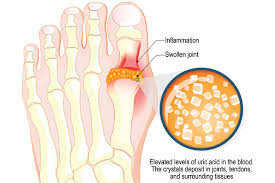

요산이란 우리가 먹는 음식이 소화되어 최종적으로 대사하고 난 후 나오는 물질입니다. 보통 혈액 내에 녹아 있다가 소변으로 배출됩니다. 통풍 환자는 혈액 내 요산이 지나치게 많습니다. 이처럼 과다 축적된 요산은 결정체로 변하고, 이 요산 결정체가 관절 내에 침착하여 염증을 유발합니다.

통풍은 요산을 생성하는 퓨린이 다량 함유된 음식을 장기간 섭취하거나 술과 기름진 음식을 많이 섭취하여 몸 안에 요산이 축적될 경우 서구화된 식습관과 운동부족 스트레스 과다 체중 증가 등으로 인해 요산이 과다 생성되며 이들이 체외로 배출되지 못하고 관절과 힘줄 등에 쌓여 극심한 통증을 유발하게 됩니다.